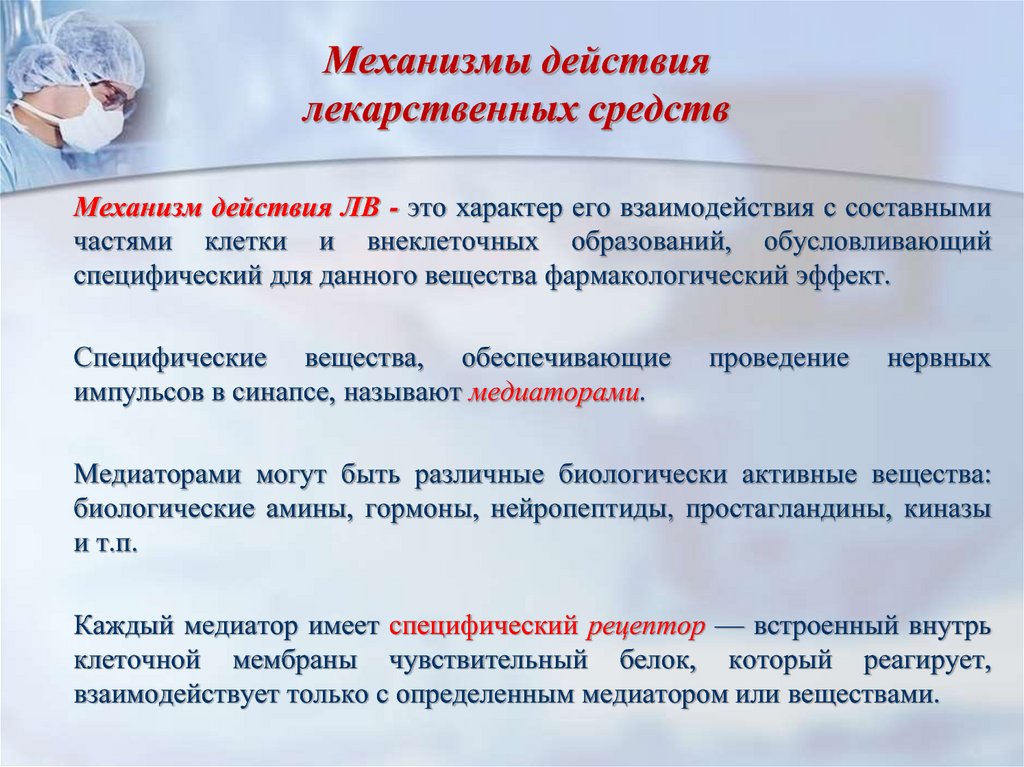

Механизмы действия антимикотиков: схемы и изображения

Раздел: Ракурсы просвещения